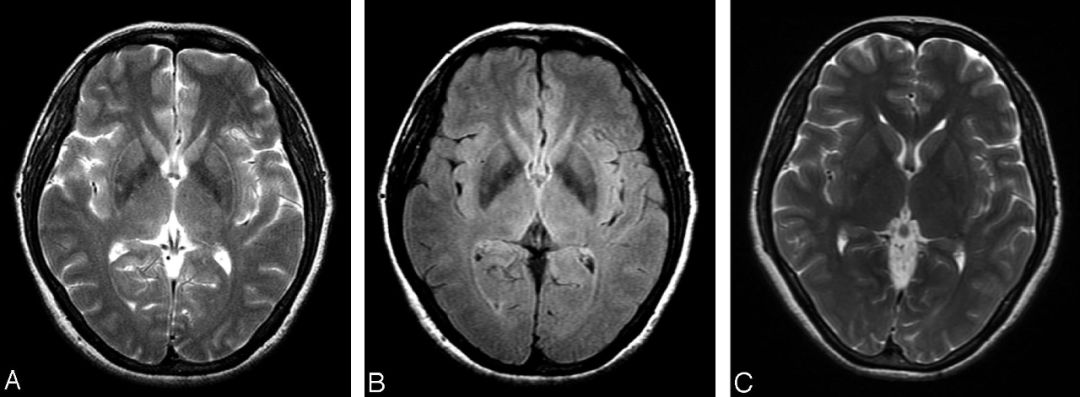

T2WI殼核后部線樣高信號,伴鐵沉積

殼核后部 T2 低信號是指在 T2WI 或 T2*殼核背外側(cè)低信號,病理證實是由于鐵蛋白丟失、鐵沉積引起。

T2WI 及 T2* 殼核鐵沉積伴部分萎縮